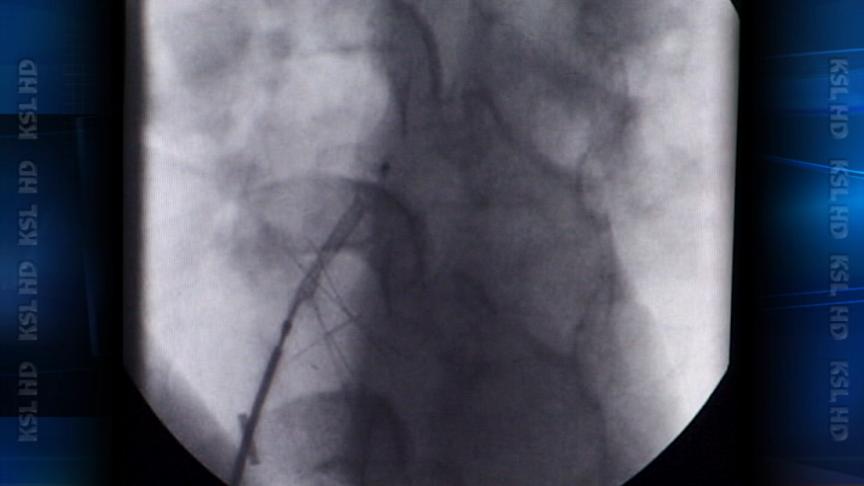

In about 35 minutes LDS Hospital surgeons in an out-patient setting, snaked a catheter up to his heart and inserted the new generation plug. Before the seal?